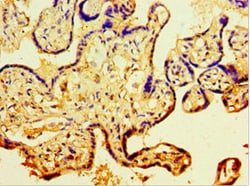

CDH11 Polyclonal Antibody for Western Blot, IHC (P), IP, ELISA

| ELISA, Immunohistochemistry (Paraffin), Immunoprecipitation, Western Blot | |